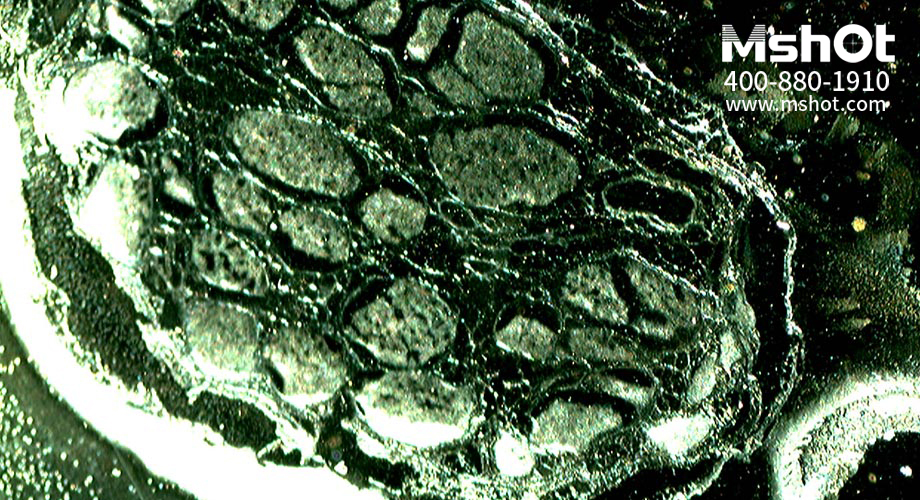

神經(jīng)纖維切片顯微圖片。 (操作提示:點擊圖片或使用鍵盤上的方向鍵來轉(zhuǎn)換要查看的圖片)